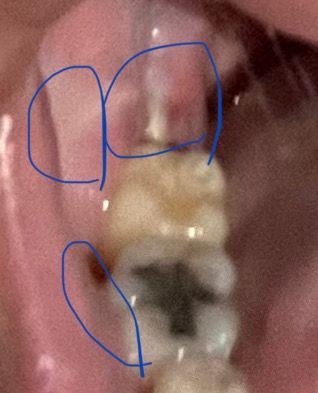

사랑니 발치 5일되었는데 드라이소켓? 치조골? 아니겠죠ㅠㅠ!?

사랑니 발치 후 5일째입니다ㅠㅠ

사진으로는 잘 안보일수도 있는데

밑에 동그랗게 표시한 부분에 흰색으로

저런 모양이 있는데 살이 차오르거나 이런 질감의 느낌이 아닌거같아서요ㅠㅠ 약간 흰색이면서 노란색입니다

혹시 드라이소켓이나 그런 증상잉 뼈 부분 일수도 있을까요?!

그리고 발치한쪽 볼에 저런 흰줄이생겼고 좀 부운거같구요,

뽑은쪽 입몸에도 흰색이있어요ㅠㅠ혹시 치조골? 그런건 아니겠죠...?! 아직 실밥은 풀기 전이에요..

3일치 약 받은거는 다 먹었고 치통도 심한건 아닌데 시큰거리고 쑤시는 정도의 느낌은 있고 약간 몸살끼랑 미열은 있는거같아서 질문드립니다ㅠㅠ 불안해서 질문드립니다ㅠㅠ

정상적인 회복 과정입니다. 시큰 거리고 쑤시는 정도로 드라이소켓을 의심하지 않으며 사진으로 흐릿하지만 특별한 이상은 없어 보입니다. 단 너무 불안하거나 느낌이 이상하다면 다시 한 번 발치한 치과 방문 후 검진을 받아보시는 것을 권해드립니다.

치조골은 아니며 치유되는 과정이라고 볼 수 있겠습니다.

드라이소켓은 감염의 일종으로 엄청난 통증이 동반되며 냄새가 심하게 날수도 있습니다. 그정도가 아니시라면 크게 걱정할껀 아니고, 걱정이 되신다면 병원에 가셔서 소독을 한번더 받으시면좋을것같습니다.

볼쪽 흰줄은 별 문제가 될것같진 않고, 전반적으로 잘 나아보이는것 같습니다.

노란색은 음식물찌꺼기가 응고된것일 가능성이 높습니다. 현재 악취가 나면서 통증이 심한게 아니라면 드라이소켓의 가능성은 적습니다.